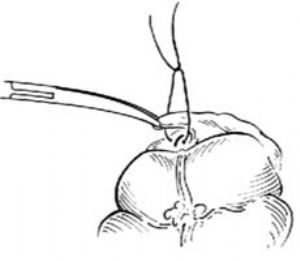

在刀刃上塗純石炭酸後,刀刃向上,緊貼闌尾根部夾緊的直止血鉗下面,切斷闌尾,將刀及闌尾一併棄去[圖1 ⑺]。

圖1 ⑺切斷闌尾